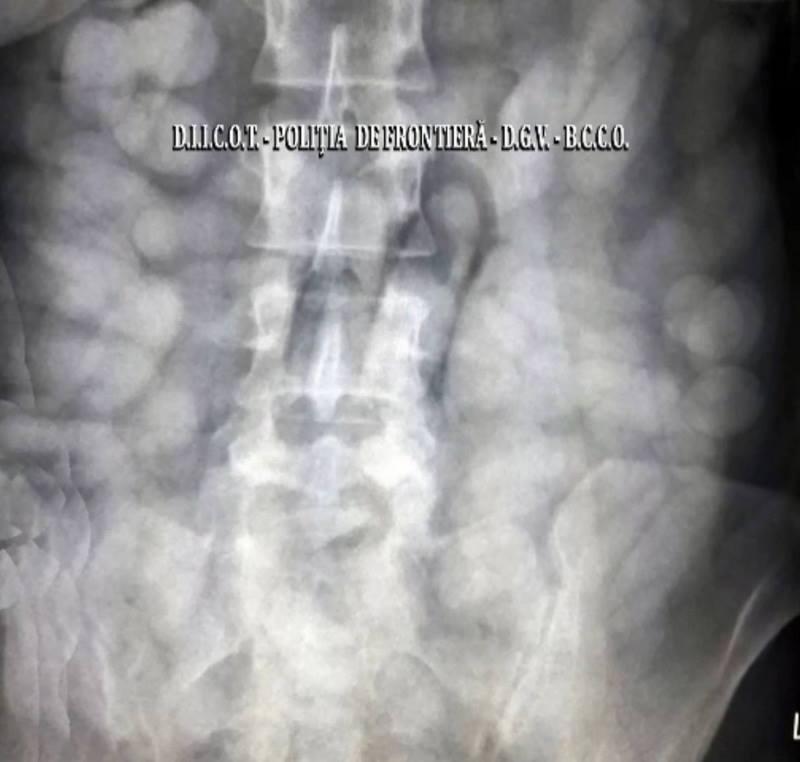

Descoperire ŞOCANTĂ pe Aeroportul Otopeni! O femeie şi un bărbat aveau în STOMAC peste 2 kilograme de cocaină!